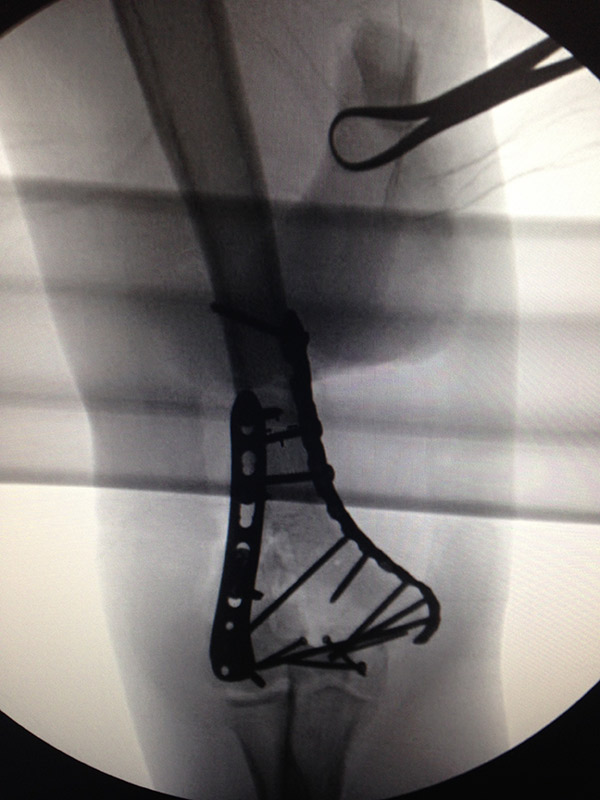

Bono has had a roller coaster ride of a year between the (however troubled) release of Songs Of Innocence and the bicycle injury that left him largely incapacitated. He used some of his time recovering from the accident to write a massive blog post looking back on what happened to him this year in a "from-A-to-Z" format. "This is too long," he began. "You should not have time to read this. If you do get to the end of it then you are probably on the same painkillers as me." Bono said that he's cancelled all of his public appearances for the first half of the year so that he can "concentrate hard to be ready for the U2 tour in fitness terms," and that "it is not clear that I will ever play guitar again," though he says that won't stop him from writing music. He also shared some photos, including one of the titanium plate in his elbow: